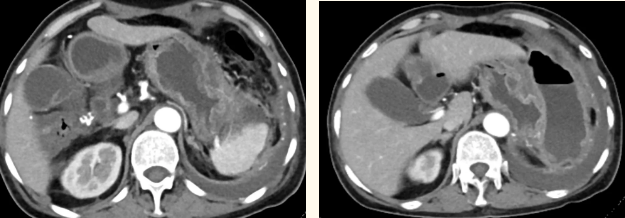

一籌莫展的她終于在病友的介紹下,來到西安國際醫(yī)學中心醫(yī)院找到蔡磊主任。經過詢問病史,查體等,蔡磊主任建議口服索坦治療。3個月后,李阿姨復查CT提示胃間質瘤較前明顯縮小,大小約10.4cm?6cm。但仍存在消化道出血,營養(yǎng)狀況差,全身無力,骨髓抑制。蔡磊主任隨即將患者收治入院。